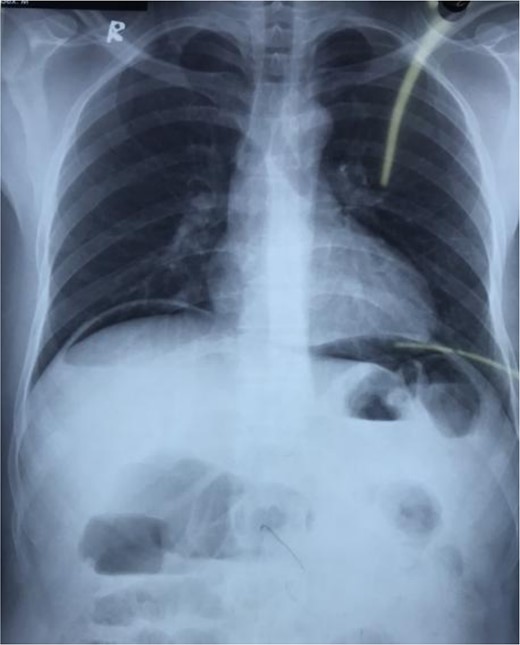

A 19-year-old thin male without known medical conditions presented to our emergency room with a 4-day history of increasingly severe abdominal pain with 3 days of fever, and repeated episodes of vomiting. He had no history of previous abdominal surgery, per-rectal bleeding, or any similar episodes. He is a smoker and consumes alcohol. He was normotensive (BP: 120/80 mmHg) and febrile (temperature: 101 F) with tachycardia (pulse: 111 bpm). On physical examination, his abdomen was distended with generalized tenderness, rebound tenderness, guarding, and rigidity. His total leukocyte count was 26 260/cu. mm, but all other hematological and biochemical parameters were normal. An erect chest X-ray revealed free air under the diaphragm (Fig. 1). An abdominal ultrasound showed moderate ascites with internal septations and moving debris.

An upright chest or abdominal X-ray is the initial imaging choice for suspected PUP and detection of free air under the diaphragm is highly suggestive and often confirms the diagnosis [2]. If X-ray results are inconclusive, an abdominal computed tomography scan is recommended for its superior sensitivity in detecting intra-abdominal free air. In our case, the erect chest X-ray of our symptomatic patient revealed free air under the diaphragm confirming the diagnosis of PUP.